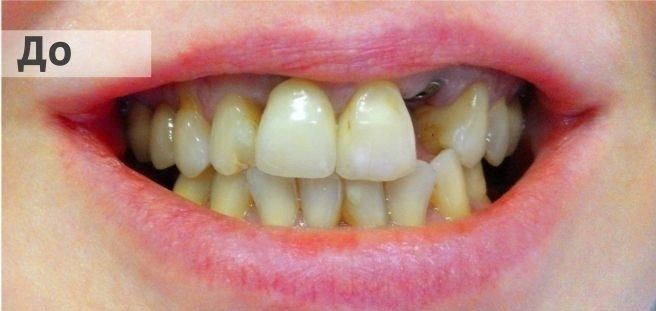

На странице представлено портфолио стоматологий Новосибирска с фото работ до и после имплантации зубов. Мы собрали разные клинические случаи: одиночные импланты, восстановление нескольких зубов и полная реконструкция зубного ряда. Здесь вы можете видеть, как выглядят восстановленные зубы, меняется форма улыбки после процедуры. Изучите результаты до и после имплантации зубов, чтобы оценить качество работы врачей и выбрать стоматологию в Новосибирске, которая поможет вернуть функциональность и эстетику вашей улыбке.

Тотальное протезирование верхней челюсти металлокерамическими коронками с опорой на имплантаты Astra-Tech (Швеция) с левой стороны, и на свои зубы с правой стороны

Тотальное протезирование верхней челюсти на 6 имплантатах Astra-Tech (Швеция)